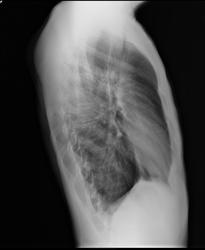

Там же сделали томограмму (снимок приложен).

В тубдиспансере по итогам анализов и рентгена поставили диагноз "инфильтративный туберкулез левого легкого I БК-". Но мне было очень трудно в это поверить, и я сделал еще КТ с контрастом у лучшего КТ-специалиста в городе. Его заключение: "Наиболее вероятно, полученная КТ-картина может соответствовать затяжному течению верхнедолевой пневмонии слева, с наличием явлений пневмосклероза и небольших очагов инфильтрации (ТВС-генез процесса представляется менее вероятным)."

Прошу вас также посмотреть рентген-снимки и КТ. Кстати, я выложил архив диска с КТ на sendspace.com, но ведь там есть личная информация, можно ли как-то скрыть ее, или опубликовать в закрытом разделе форума? Пока не стал выкладывать ссылку сюда.

Если все-таки диагноз верен, то насколько он страшен, не видно ли на снимках распада? Просто очень боюсь заразить ребенка и беременную жену... Лечение все-таки решил начать завтра-послезавтра, после сдачи последних анализов.

Рентген сбоку 27.09.2013: